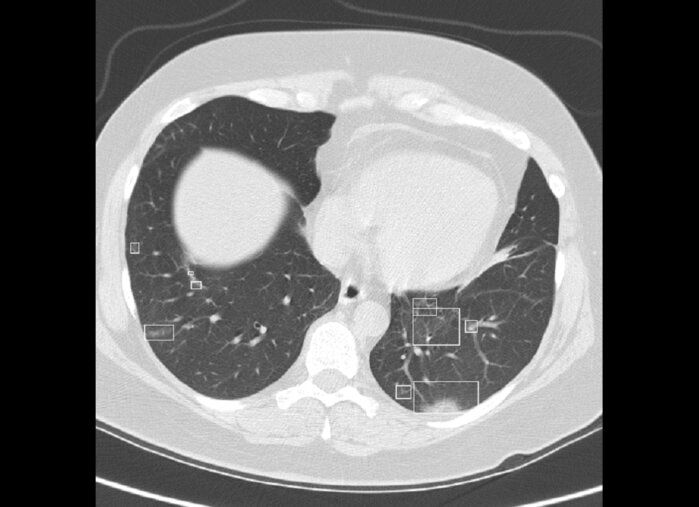

Исследователи из Google AI, Северо-Западного университета в Чикаго и других организаций разработали нейросеть, способную обнаружить рак лёгких по томографическим снимкам, сообщает Nature. Алгоритм даёт шанс пациентам на своевременное лечение, выявляя опухоль на ранних стадиях.

За счёт глубокого обучения ИИ становится всё более опытным помощником с каждым новым снимком, достигая высокой точности решений. Учёные продемонстрировали это, опубликовав свои результаты в Nature Medicine в 2019 году. Нейронная сеть поставила верный диагноз в 94% случаев, опередив группу из 6 врачей-рентгенологов.

Диагностика рака лёгких по данным компьютерной томографии улучшается благодаря опциям КТ Легких от российской команды СберМедИИ. Сервис использует искусственный интеллект для обработки КТ-снимков, которые были собраны во время пандемии COVID-19. Таким образом, ретроспективный анализ позволяет медицинским учреждениям провести массовый скрининг населения по уже имеющимся архивам КТ исследований:

• алгоритмы автоматически распознают мелкие узловые новообразования в лёгочной ткани;

• если они превышают минимальное пороговое значение в 4 мм, ИИ выделяет их;

• рентгенолог обращает внимание на подсвеченные участки и учитывает их при постановке диагноза.

Сервис КТ Легких автоматизирует визуальный поиск патологических зон. Это помогает врачам оперативно и точно выявить лёгочные новообразования.